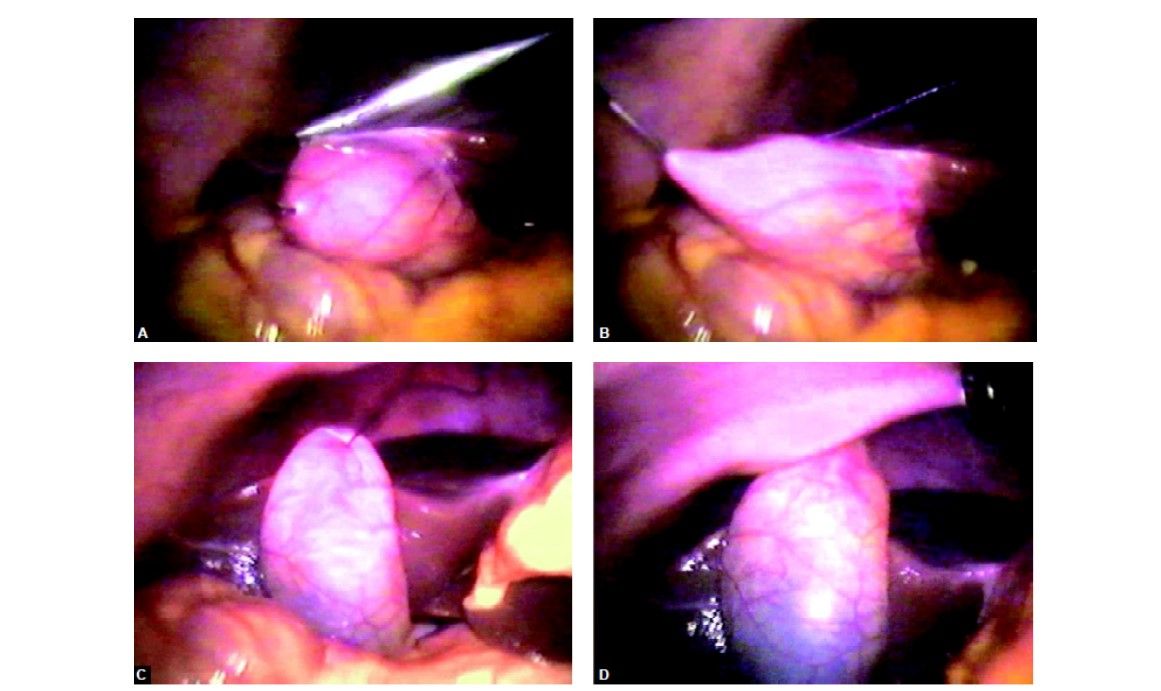

An extracorporeal knot can be applied for a cystic duct without any problem after a nice dissection of the cystic pedicle. The knot which is tied over the cystic pedicle is used to pull the neck of the gallbladder up and with the help of hook GB is separated from the liver. Patients undergoing cholecystectomy by the two-port method had a better resumption of diet and less postoperative pain. Two-port cholecystectomy is technically feasible and may further improve the surgical outcomes in terms of postoperative pain and better cosmetic value. The two-port cholecystectomy should be performed by an experienced laparoscopic surgeon because skilled choreographic hand movement is very important in this surgery. Bimanual skill and correct interpretation of anatomy is a must before proceeding for this technique. We do not recommend two-port cholecystectomy as a routine procedure.

The extracorporeal knot of the cystic duct is used to pull the neck up and to expose bed of the gallbladder

Any leak should be sucked and gallbladder is separated with the help of hook